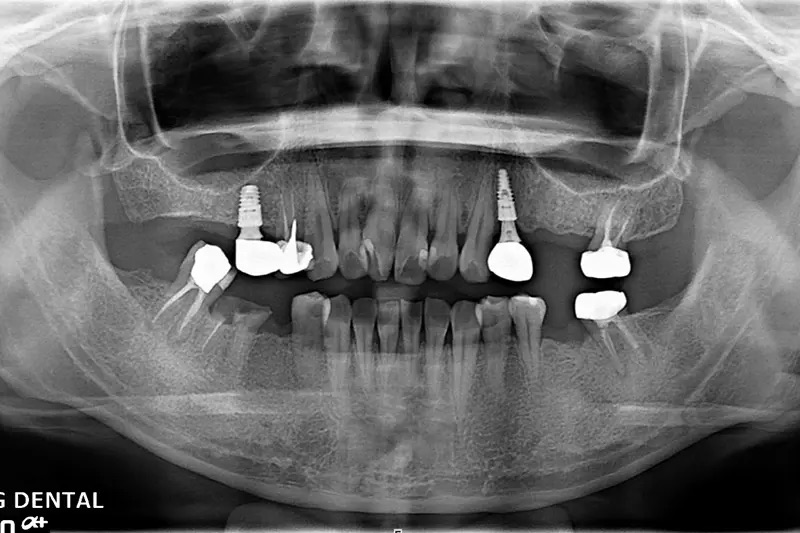

植牙成功案例